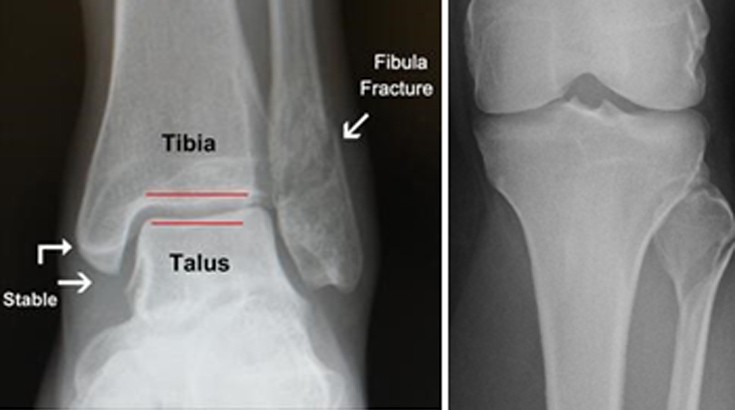

Αυτό συμβαίνει γιατί τα δύο οστά συγκροτούν μία κολώνα με δύο στηρίγματα. Όταν σπάσει η μία κάπου, πρέπει να σπάσει και η άλλη (καμιά φορά αντί να σπάσει, κόβεται ο δελτοειδής σύνδεσμος ή υφίσταται κάταγμα η κεφαλή της περόνης στο γόνατο (κάταγμα Maisonneuve).

Στα κατάγματα των σφυρών επειδή διαταράσσεται η άρθρωση (υπεξάρθρημα – εξάρθρημα) μετά την κάκωση ο τραυματίας αδυνατεί να πατήσει το πόδι του και να βαδίσει και η άρθρωση φαίνεται πολύ διογκωμένη και παραμορφωμένη.

Με το δάκτυλο ψηλαφώντας ανευρίσκουμε μεγάλη ευαισθησία ή στο έσω και στο έξω σφυρό. Ο τραυματίας δεν μπορεί να κάνει τις φυσιολογικές κινήσεις, δηλ. της ραχιαίας έκτασης και την πελματιαία κάμψη.